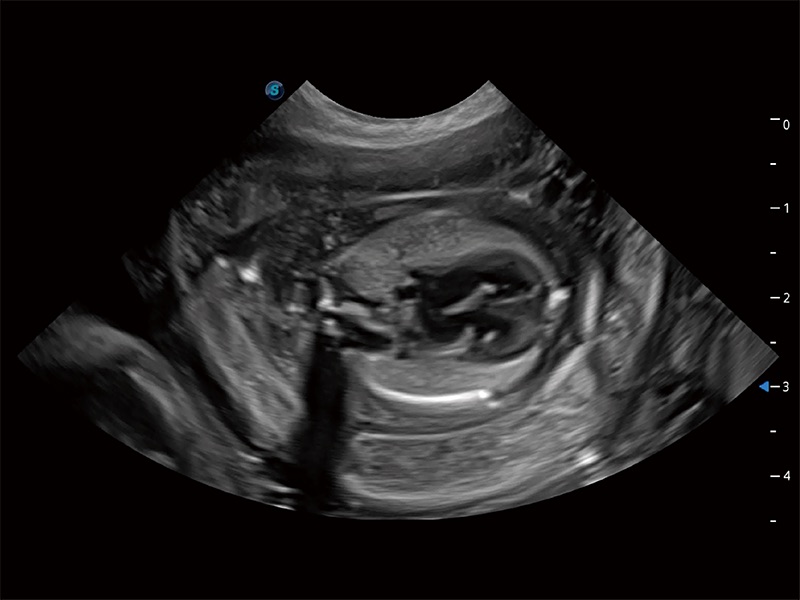

ProPet 80 配备了丰富的心脏探头群、先进的成像技术和专业的心脏测量工具,可帮助动物医生为不同体型和生理结构的动物提供心脏和心肌功能的全面评估。

ProPet 80 专为动物医生设计,对不同的动物体型和生理结构作出了针对性的优化。通过动物影像专用软件,可满足个性化的应用需求,帮助动物医生获得更精确的诊断数据。